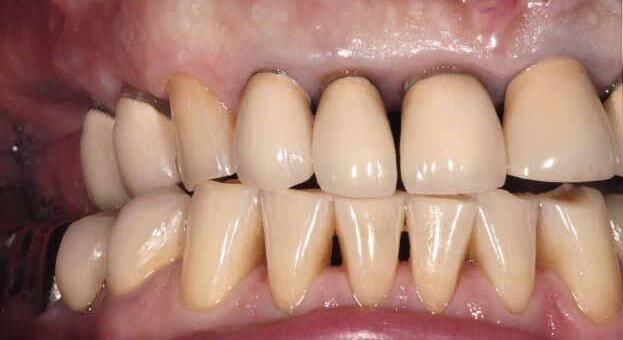

A significant number of people are unhappy with their smile, which has a considerable psychosocial impact. Although many seek cosmetic dental treatment, costs, fear and duration of total treatment are often barriers to the patients. Nevertheless, many could benefit from small and subtle changes to their teeth. With simple direct and freehand techniques, quick but significant results can be obtained that ultimately greatly improve the overall smile aesthetics.

The restoration of abfractions in the anterior area is important for aesthetic appearance especially in patients with high smile lines. Moreover, restoring abfractions strengthens the cervical area of the tooth, prevents further loss of enamel and ameliorates unpleasant sensitivity.

Black triangles and diastemas can cause entrapment of the food and accumulation of bacteria, which leads to gingivitis and ultimately periodontitis. By eliminating the black triangles and diastemas with composite bonding, the dentist not only improves the aesthetics, but also protects the long-term health of the periodontal tissues.

Worn canine cusp restoration is of special functional importance. Creating functional canine guidance with a minimally invasive composite addition to the canine cusp will protect the posterior teeth during lateral movements of the jaw. Incisal wear restorations return the youthful appearance to the smile and prevent further loss of enamel and exposure of the dentinee.

Restoring incisal wear and closing diastema with G-aenial A’CHORD. Courtesy of: Dr Aleksandra Slacan, Poland

Reshaping of teeth and diastema closure with G-aenial A’CHORD. Courtesy of: Dr Andres Silva, Spain